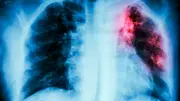

Das niedersächsische Landesgesundheitsamt warnt vor der Ausbreitung der Frühsommer-Meningoenzephalitis. Virologe Masyar Monazahian betont, dass Zeckenkontakte im Alltag häufig unterschätzt werden.